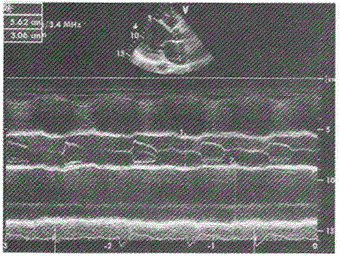

M型超声心动图主动脉瓣开放幅度,正常成人应大于

- E.16mm

正常成人主动脉瓣开放幅度>16mm。